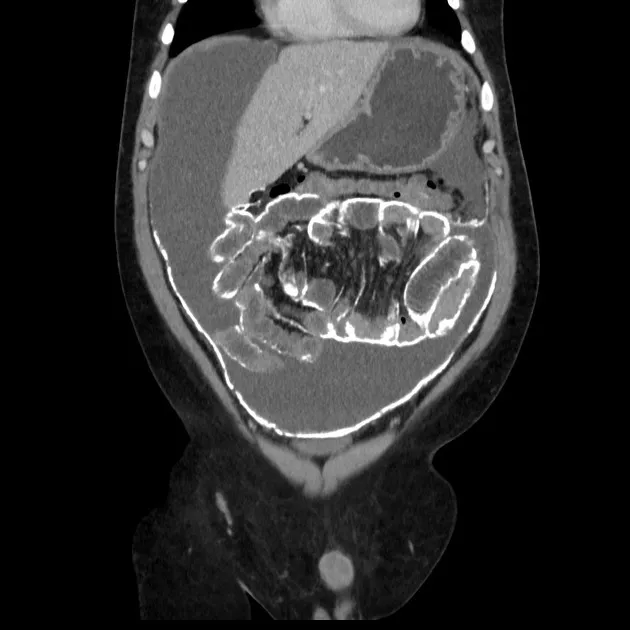

A DRPAD não é contraindicação à DP — e, na prática, muitos pacientes têm resultados comparáveis à hemodiálise. O “porém” está na mecânica: rins/hepatomegalia podem reduzir tolerância a volumes, aumentar risco de hérnias e extravasamentos, e piorar desconforto respiratório. Com técnica adequada (cateter presternal ou lateral, volumes menores, cicladora noturna e decúbito supino), a maioria das barreiras é contornável. Neste post, revisamos quando a DP é ótima, quando exigir cautela e como ajustar a prescrição para segurança e qualidade de vida.